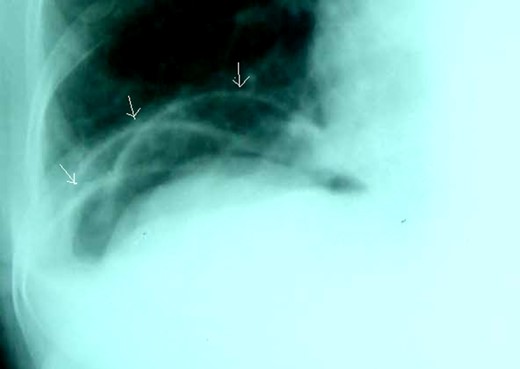

Plain supine abdominal radiograph showed features of small bowel obstruction. However, a plain chest radiograph taken in erect position showed radiolucent shadow under the right dome of the diaphragm, first simulating pneumoperitoneum (Fig. 1). The impression of free gas under the diaphragm was very much supported by the clinical finding of obliterated liver dullness. However, on careful examination of the radiograph, few semilunar radio-opaque linings could be seen, which could be walls of bowel loops (Fig. 2). She was diagnosed as acute intestinal obstruction, probably Chilaiditi's syndrome: we thought of obstruction due to herniation into the hepatodiaphragmatic space.

Careful examination showing semilunar opaque lines which were walls of small bowel loops (arrows).